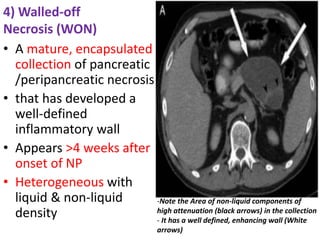

4) Walled-off

Necrosis (WON)

• A mature, encapsulated

collection of pancreatic

/peripancreatic necrosis

• that has developed a

well-defined

inflammatory wall

• Appears >4 weeks after

onset of NP

• Heterogeneous with

liquid & non-liquid

density

-Note the Area of non-liquid components of

high attenuation (black arrows) in the collection

- It has a well defined, enhancing wall (White

arrows)